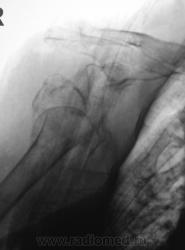

Пол пациента: Женский пол Тип патологии: Травма Область исследования: Скелетно-мышечная система Методы исследования: Rg Мы, ранее демонстрировали и "первичный" снимок и снимок после наложения "гипсовой повязки", вот он... https://radiomed.ru/sites/default/files/styles/case_slider_image/public/user/12/22.Pervyy.P4290004a.jpg?itok=J8w9QKuH ID:3524 Пт, 30/04/2010 - 23:44 #1 Катенёв Валенти... Не на сайте Был на сайте: 7 лет 3 недели назад Зарегистрирован: 22.03.2008 - 22:15 Публикации: 54876 Конечно, в протоколе все было подробнейшим образом описано. Какое же было удивление, когда через месяц, "гипсовая повязка" была снята... и пациентка была направлена на "контроль" с целью подтверждения "консолидации перелома". Приложения: Сб, 01/05/2010 - 10:00 #2 Vikkur Не на сайте Был на сайте: 4 года 8 месяцев назад Зарегистрирован: 24.09.2009 - 14:34 Публикации: 1749 НО комент..."Вечно эти рентгенологи понапишут" Виктор. Чт, 13/05/2010 - 16:49 #3 Сан Саныч Не на сайте Был на сайте: 15 лет 6 месяцев назад Зарегистрирован: 23.04.2010 - 20:23 Публикации: 73 !!!!!!!!!!!!!!!!!!!!!!

Конечно, в протоколе все было подробнейшим образом описано.

Какое же было удивление, когда через месяц, "гипсовая повязка" была снята... и пациентка была направлена на "контроль" с целью подтверждения "консолидации перелома".